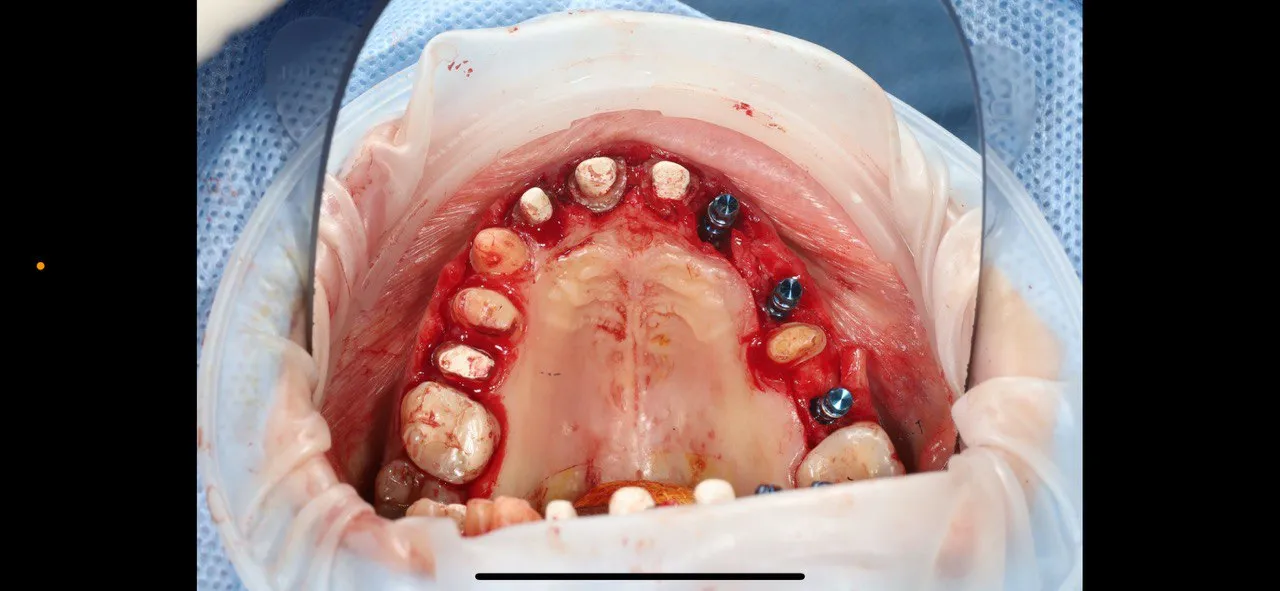

Before-and-after dental implant surgery with guided protocols

Guided implant placement with simultaneous bone augmentation